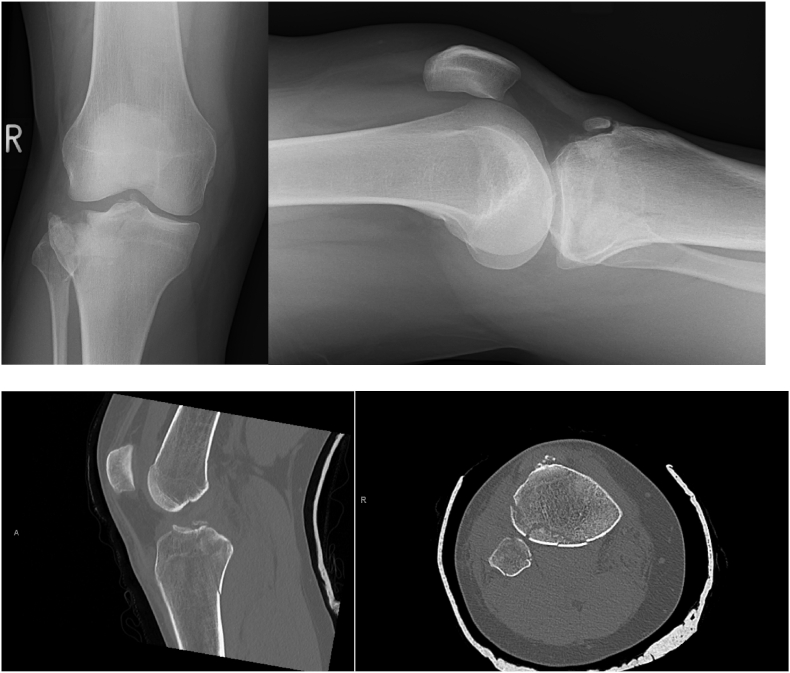

Fig. 2.

Example imaging showing a posterior shear component that was not immediately apparent on the original radiograph. All surgeons opted for a lateral incision and plate in the supine position in round one. In round two, three surgeons opted to fix the posterior fracture, two altered position and three changed their approach.